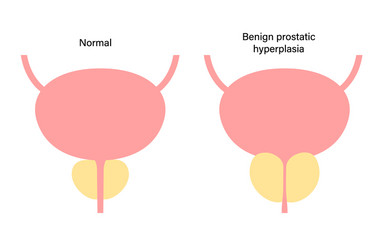

- Urinary

- Enlarged

- Prostate

- Bladder

- Anatomy

- Disease

- Disorder